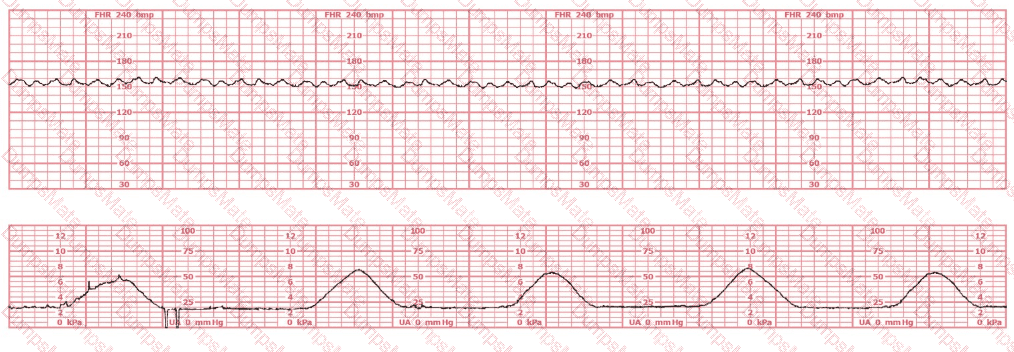

Questions 27

A woman at 38-weeks gestation is admitted to labor and delivery following a fall down the stairs three hours ago. She started feeling contractions in the ambulance. The fetal heart rate tracing shown is on initial evaluation and represents 25 minutes. This tracing is most consistent with a

EFM Question 27

Options:

A.

category I tracing

B.

category II tracing

C.

category III tracing